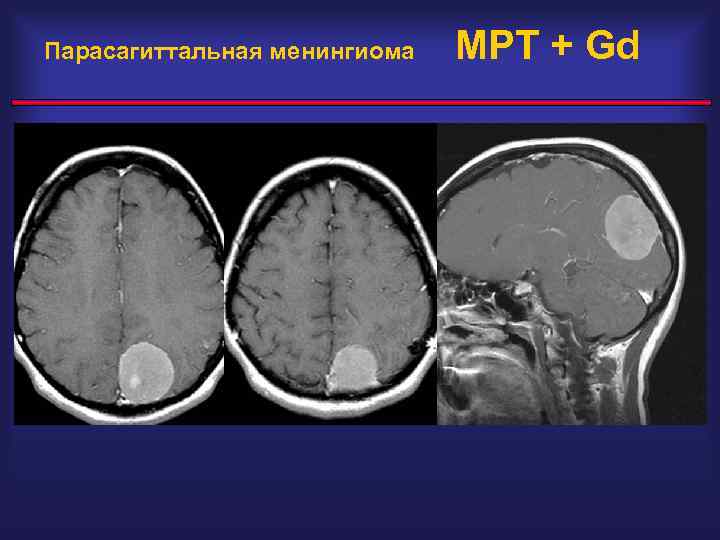

Парасагиттальная менингиома

Парасагиттальная менингиома МРТ + Gd